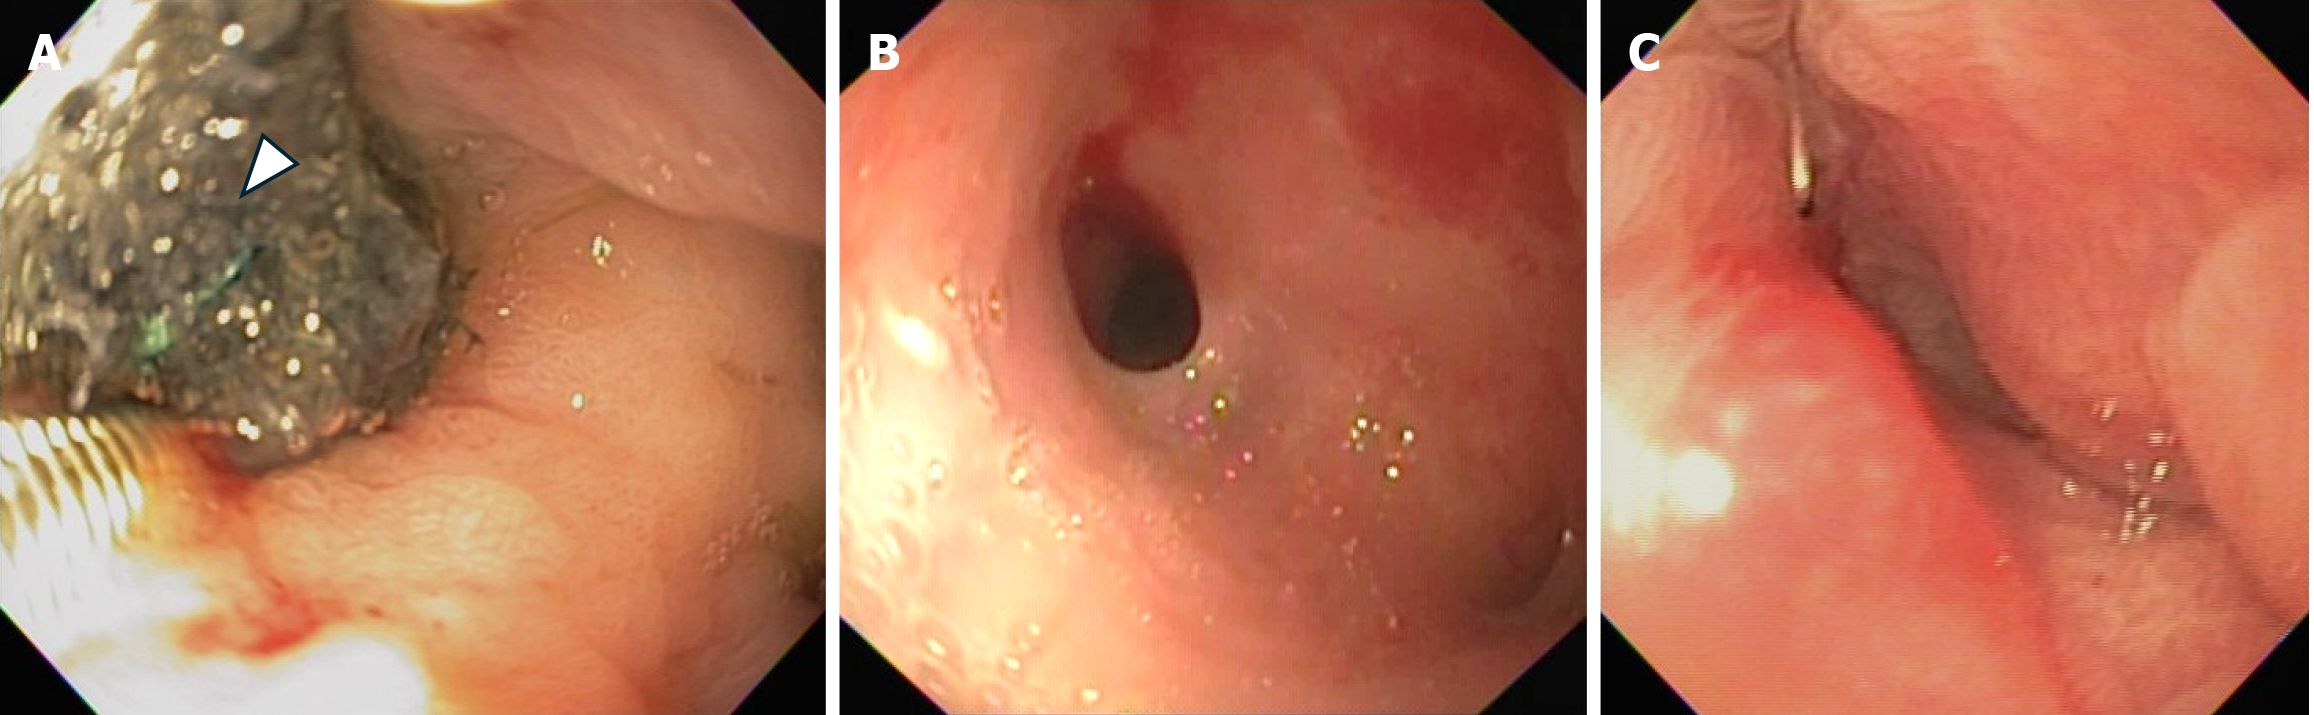

Figure 2 Esophagogastroduodenoscopy images during treatment.

A: Endoscopic vacuum therapy with a polyurethane sponge (arrow heads) applied to the fistula orifice; B: Marked reduction in fistula size; C: Successful closure of the fistula.